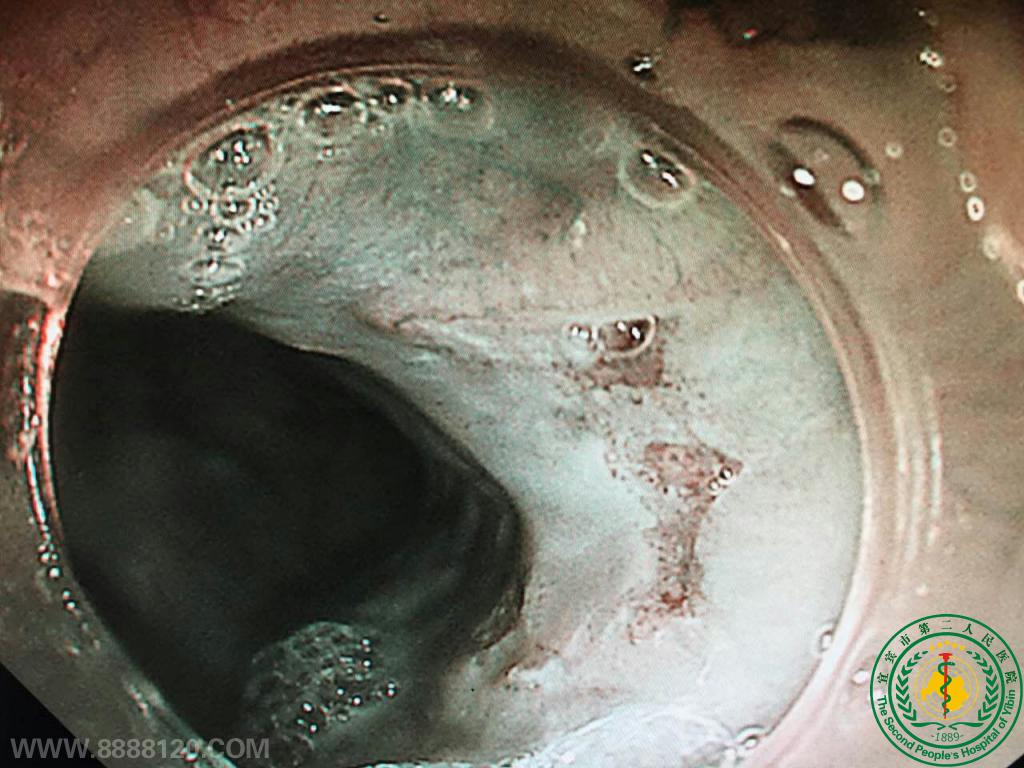

消化科成功实施宜宾市第一例早期食管癌胃镜下切除

消化科成功实施宜宾市第一例早期食管癌胃镜下切除11290